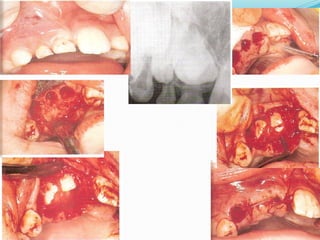

Management of buried teeth

 Buried teeth (including supernumeraries) are

treated in children for several reasons -

1. Symptomatic (eg. pain)

2. Radiographic sign of pathology (eg.dentigerous cyst

formation)

3. Part of an orthodontics treatment plan

Extraction Of Buried Teeth

 Flap design

Flap should:-

1. be muco-periosteol.

2. Be cut 90º to bone.

3. Have a good blood supply.

4. Avoid damage to imp. Structures

5. Allow atraumatic reflection.

6. Provide adequate access and visibility.

7. Permit re-apposition of the wound margins over

sound bone.

 Bone Removal

this may be carried out using a hand piece and bur

or by the use of chisels.

 Tooth Removal

once sufficient bone has been removed to allow

identification of the tooth to be extracted &

exposure of the greatest diameter of its crown, the

tooth should be elevated.

 Suturing